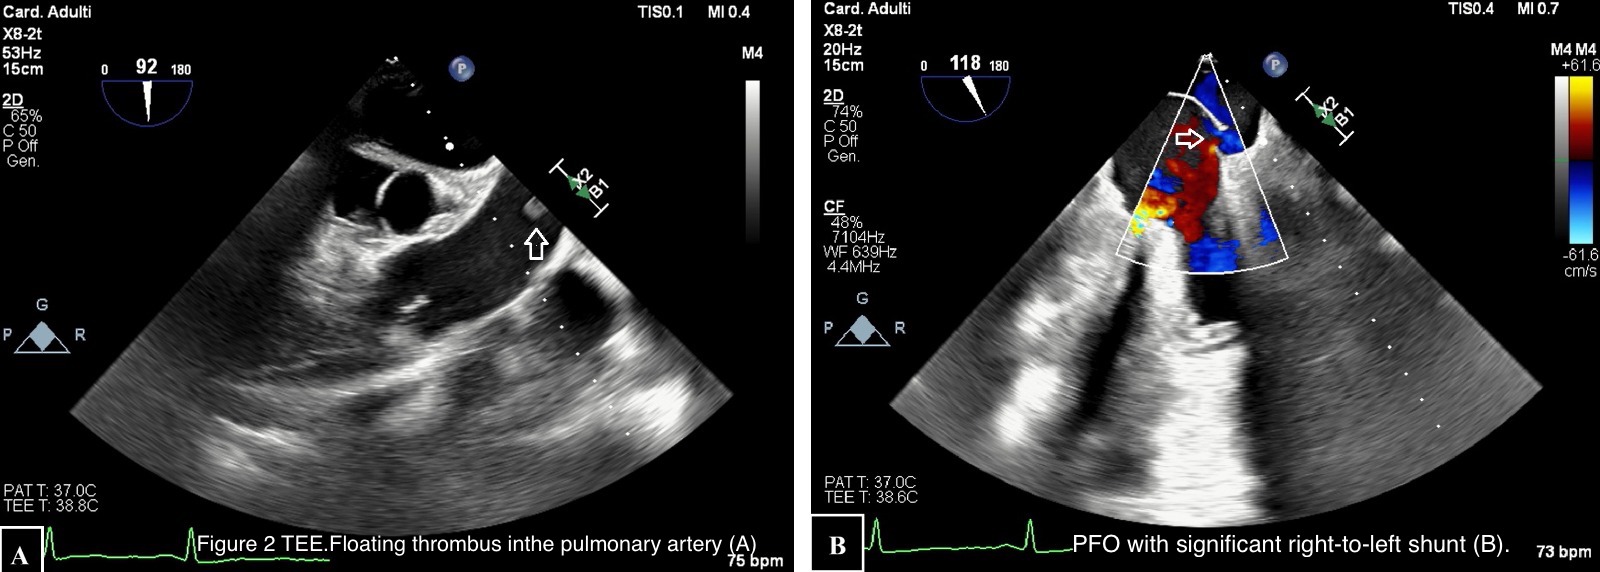

Introduction Ischemic stroke (IS) is caused by the obstruction of cerebral blood vessels, resulting in reduced blood flow and impaired oxygen delivery. It can be caused by atherothrombotic occlusion of large arteries, cerebral embolism or non-thrombotic occlusion of small, deep cerebral arteries. Cardioembolic IS can occur in the presence of various cardiac conditions, such as cardiac masses, patent foramen ovale (PFO), endoluminal thrombosis and sometimes as complication of infective endocarditis (IE). We present the case of a patient admitted to Intensive Care Unit (ICU) after non-cardiac surgery (NCS) who developed IS with high suspicioun of cardioembolic origin. Case presentation A 67-year-old man admitted to ICU developed right-sided hemiparesis after laparoscopic enterolysis surgery. His past medical history included a previous intestinal resection for ischemia. Computed tomography (CT) confirmed IS (1) , suspicious for embolic origin. Atherosclerosis of large cerebral vessels was excluded. Due to post-operative fever, blood cultures were collected and an infection caused by S. Aureus and M. Morganii was detected. Transoesophageal echocardiogram (TEE) was performed to confirm the suspicion of IE with embolization. TEE showed PFO with a significant right–to-left shunt (2B) . Moreover, a floating thrombus was detected in the pulmonary artery (2A) . No IE was found. CT angiography confirmed pulmonary thromboembolism (PE) (3) . Unfortunately, the patient died because of post-operative complications. Discussion The peculiarity of this case is represented by the unexpected aetiology of IS considering the clinical confounding presentation. At first, the most probable expected cause was represented by IE but PE and paradoxical embolization due to large PFO turned out to be responsible of IS. Some studies demonstrate PFO association with increased risk of IS in patients undergoing NCS in different settings. The prevalense of PFO in the general population is estimated at approximately 20-25% but the lack of a systematic screening in patients without IS likely underestimates its prevalence. Currently, PFO closure in addition to anti-aggregation therapy is indicated in patients with IS when a strong causal relationship between PFO and stroke is demonstrated. Further prospective trials are needed to identify a specific population at risk of perioperative IS associated with PFO in order to define systematic screening, prevention plans and improve perioperative outcomes.